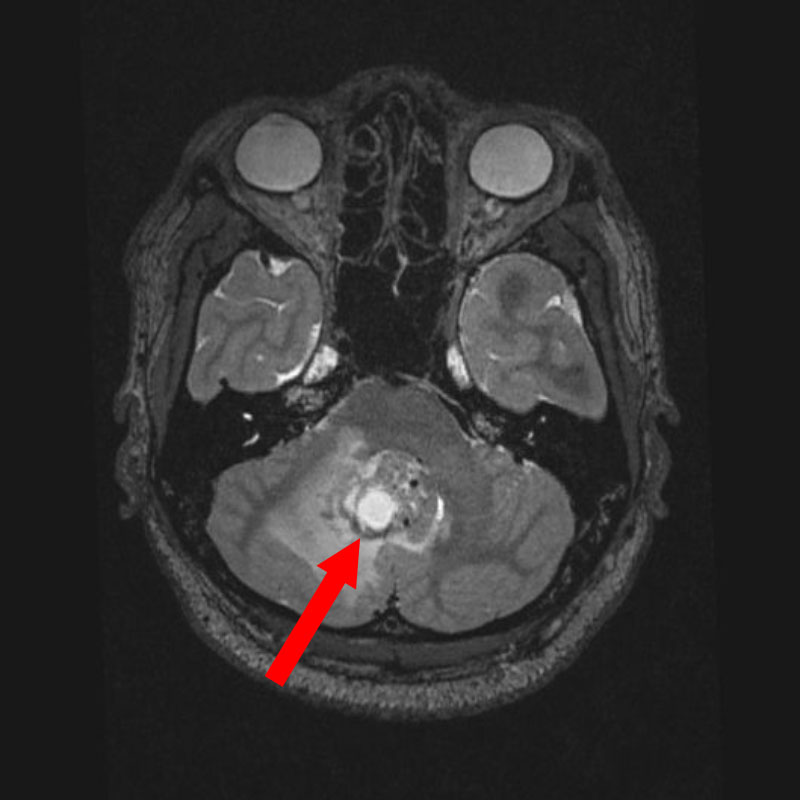

680

'25年10月

30代

小脳腫瘍

頭蓋内腫瘍摘出術

No.’25_82 手術前1

No.’25_82 手術前2